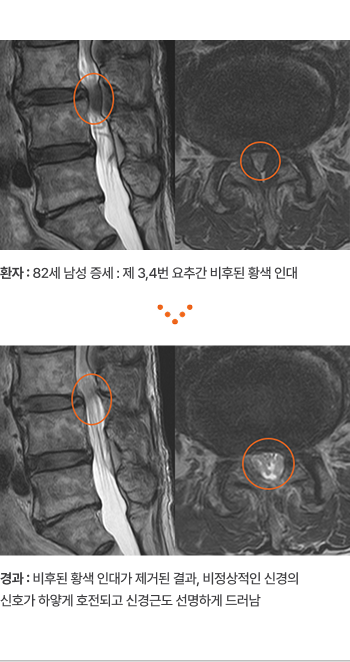

환자 :

82세 남성 증세 : 제 3,4번 요추간 비후된 황색 인대

경과 :

비후된 황색 인대가 제거된 결과, 비정상적인 신경의 신호가 하얗게

호전되고 신경근도 선명하게 드러남